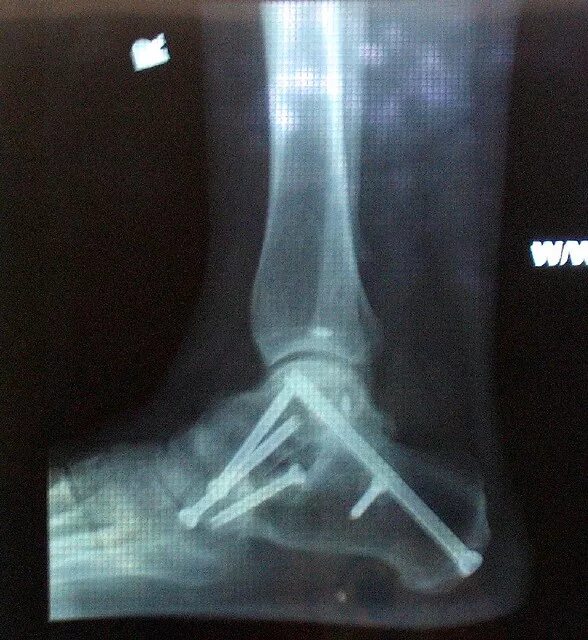

Артродез форум